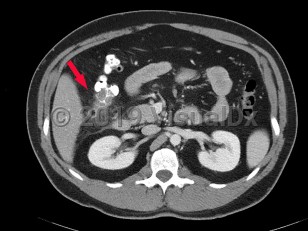

Diverticulitis is a disease characterized by inflammation in colonic diverticula. Cases are classified as uncomplicated or complicated on the basis of clinical and radiographic features. Uncomplicated cases are characterized by clinically stable patients with inflammation in a localized area of the bowel wall. By contrast, complicated disease is defined by the presence of abscess, phlegmon, fistula formation, obstruction (large bowel, small bowel), bleeding, perforation, or peritonitis, which are collectively present in about 12% of cases.